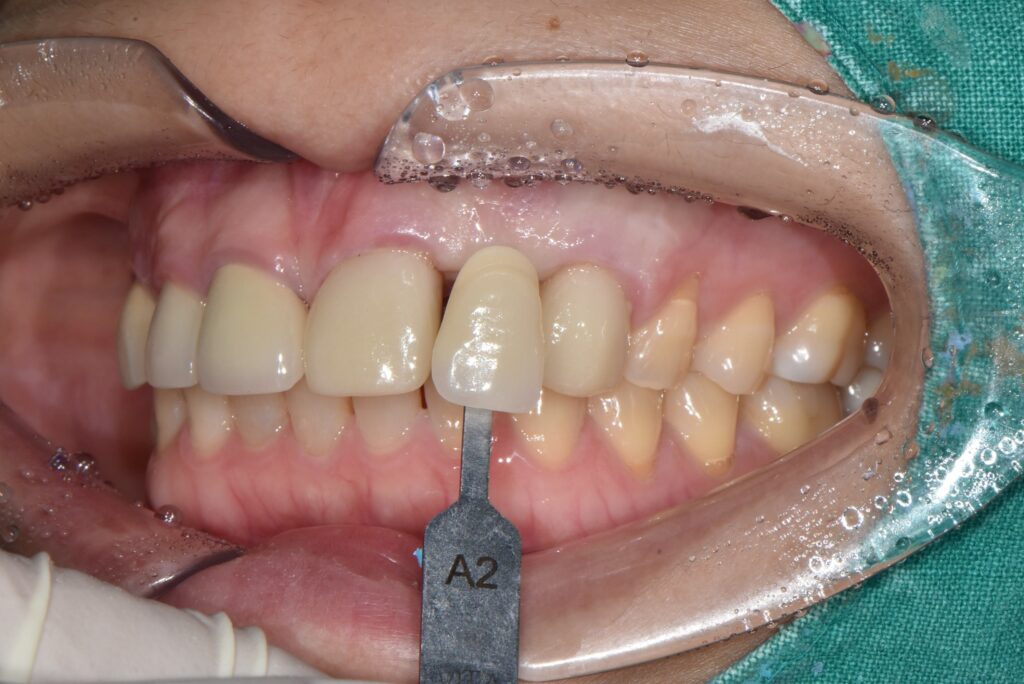

상태 체크를 위해 구내 사진과 엑스레이 촬영을 먼저 하였습니다!

치아 한 개가 상실되어 양 옆 치아를 연결해서 만든 보철물을 브릿지라고 하는데요.

브릿지가 빠져있고 남아있는 치아를 보니 연결해서 쓰던 치아 내부에 2차 충치가 생겼습니다.

사실 상태가 좋지 않아 발치 가능성이 높았지만 최대한 자연 치아를 살려보고자 치료를 들어갔어요 ‘-‘

크라운과 임플란트 보철이 완성된 모습입니다!

임플란트 보철물도 주변 자연치아와 잘 조화되어

큰 이질감이 없어요!!